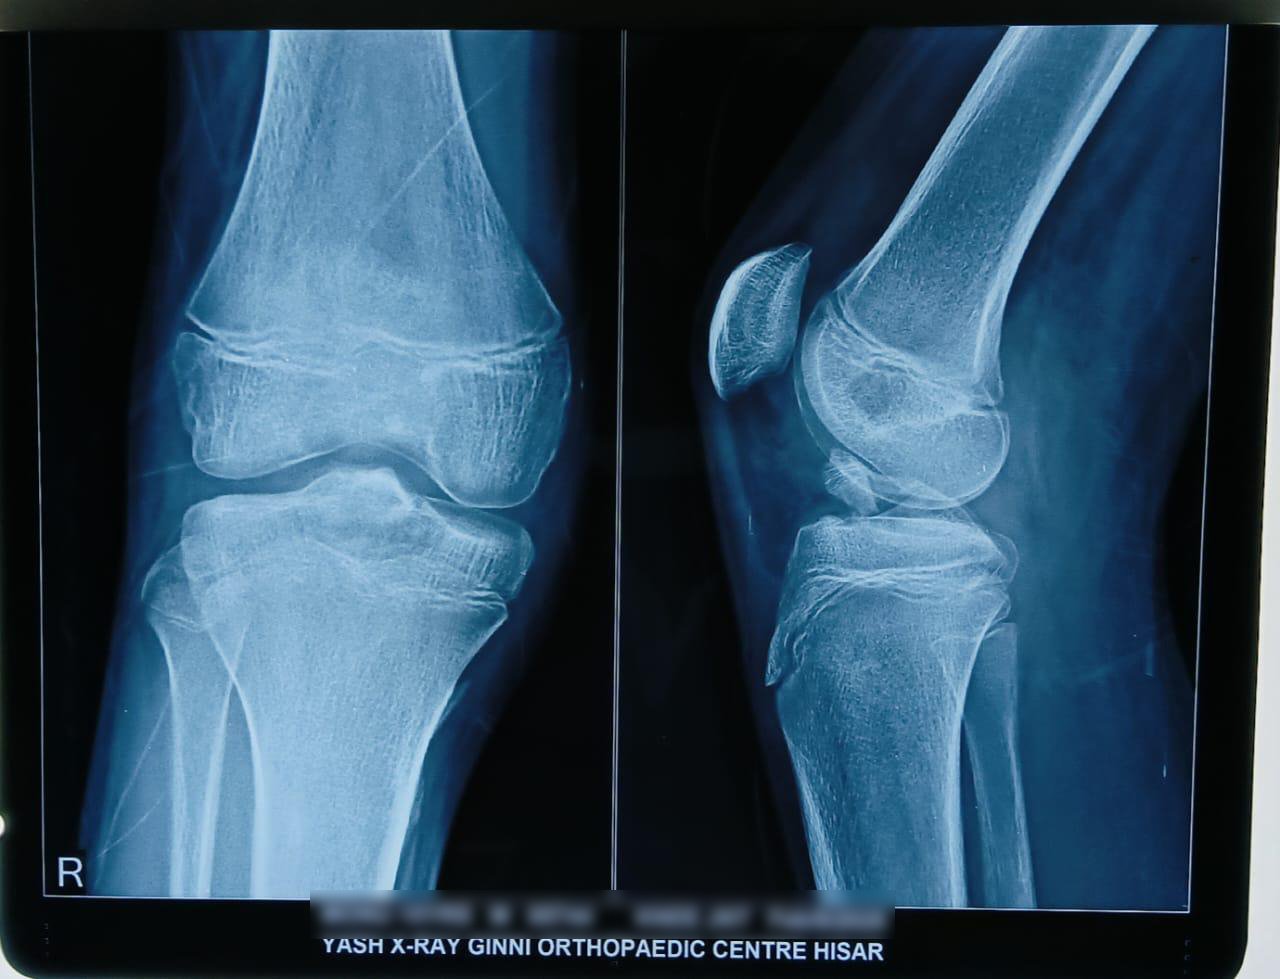

• X-rays: For bones/fractures